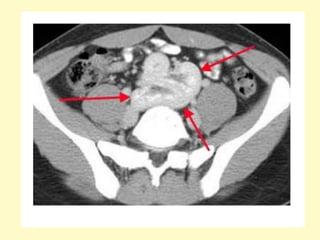

Ectopic pelvic kidney, Volume rendering (a) demonstrates absence of the left

kidney at the left renal fossa, instead, an ectopic left pelvic kidney is seen,

the axial contrast-enhanced MDCT image (b) shows an engorged left iliac

vein (asterisk), due to left aberrant renal vein (not shown), the ectopic

kidney receives blood supply from two renal arteries arising form the aorta

(arrowhead) and left iliac artery (arrow)